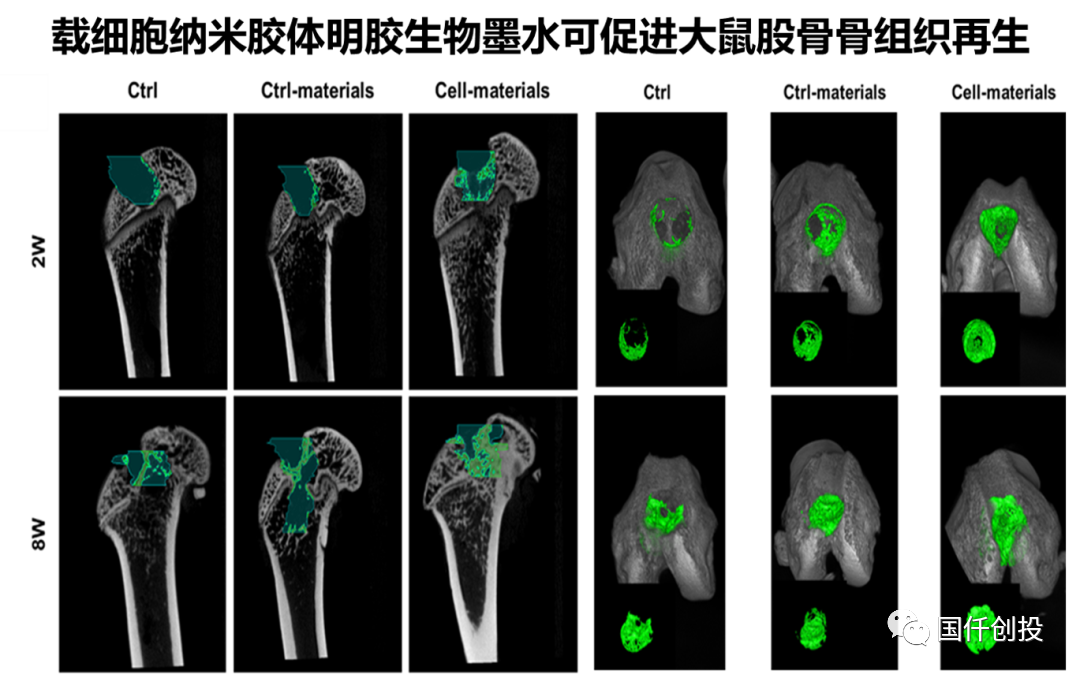

HN-GC生物墨水搭載骨髓基質(zhì)細(xì)胞MSCs打印得到支架材料,植入大鼠股骨缺損部位8周后,觀察到顯著促進(jìn)骨組織修復(fù)再生。